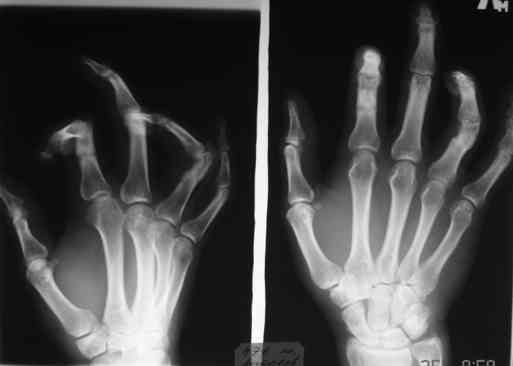

Уважаемые коллеги!Обратился больной с контрактурой 2-4 пальцев кисти. Травма год назад - рука попала в шнек. Планируется оперативное лечение.

При размещении с рисунков "исчезли" подписи, поэтому дополнительно указываю, что первая рентгенограмма - снимок после травмы, вторая - состояие на сегодня. На мой взгляд контрактура прежде всего артрогенная, т.к. ПМФС 2-го и 4-го пальцев находятся в подвывихе. Движения, в существующем на сегодня объеме, свободные - даст-ли тендолиз ожидаемый эффект? Стоит-ли начать с аппарата внешней фиксации? Не приведет-ли одномоментный артролиз и последующая попытка вправления при длительно существовавшем подвывихе к раздавливанию суставными поверхностямя друг друга?

Для того, чтобы понять, действительно ли ПМФС находятся в подвывихе, надо сначала сделать четкую боковую рентгенографю сустава. Особенно это касается второго пальца. Да и на мониторе очень плохо видно состояние головки проксимальной фаланги 4 пальца. И что означает такой интересный объем движений в суставах? Объясните - существует ограничение только активных движений ( и каких?) или еще и пассивных?

Ограничение движений одинаковое и активных и пассивных. Движения в указанном объеме свободные. Чем вызвано ограничение понять пока не можем. В боковой проекции досняли - получается, что подвывиха нет. Вопросов, в отношении того, что мешает стало еще больше.

Да, забыл. Третий палец я бы вообще не трогал или ограничился только лишь небольшой редрессацией ( насколько я понял по картинкам и описанию - ограничение пассивно-активной функции на 3 пальце - абсолютно минимальные).